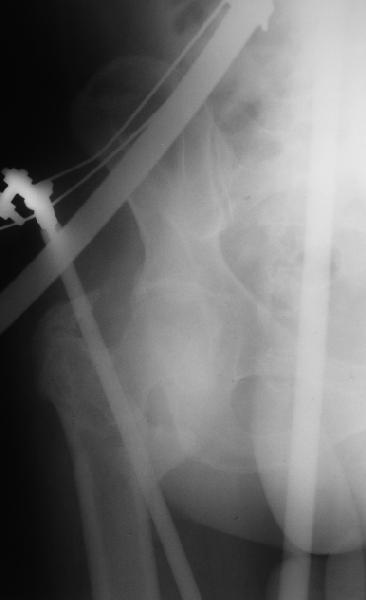

На прошлой неделе оперировали похожего пациента. 2 года после неудачного остеосинтеза PFN в другом регионе. После удаления остатков железа выявилось несращение вертельной области.

Если есть сильное желание фиксировать все-таки гвоздем, советовал бы ввести мощный "джойстик" параллельно оси шейки бедра близко к ее задней стенке, сделать поперечную межвертельную остеотомию и использовать дистрактор таз-бедро.

Поскольку в нашем случае выявилась подвижность, мы наложили дистрактор таз-бедро на 3 дня, и сделали остеосинтез гаммой без остеотомии. То, что произошла "корригирующая остеоклазия" в подвертельной области, выявили после введения гвоздя. Пациент уже уехал домой, будем наблюдать.